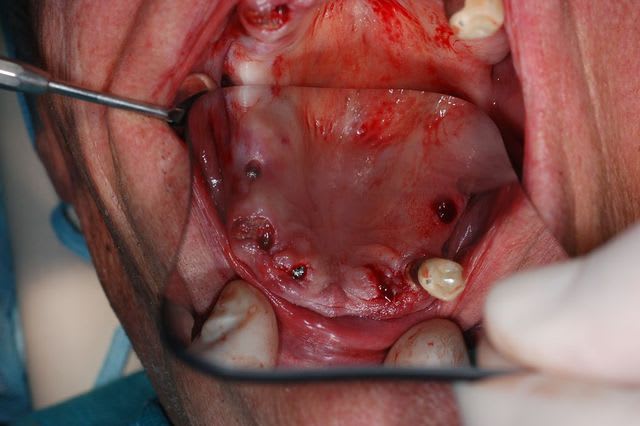

C'est une question que je me pose, car je viens de faire un cas comme ça mercredi matin.

Au départ j'avais plutôt prévu de faire un lambeau d'accès comme d'habitude avec sutures et tout et tout...

Étant donné que j'avais une autoroute en matière de crête osseuse, je me suis dis " et puis zut, restons dans le couloir prothétique et plantons en aveugle".

Une bonne connaissance du scan était nécessaire, et des petits contrôles radios pendant la pose bien évidemment pour connaître la longueur de perçage et savoir quand mon implant allait être juxta-crestal.

petits commentaires:

- J'ai trouvé ça super de ne pas avoir à faire de sutures

- l'un des implants est volontairement incliné car il vient longer le plancher sinusien. Je n'avais pas envie de faire de Summers et le patient ne voulait pas de soulevé de sinus.

Est ce que les cellules gingivales vont réduire mes chances d'ostéointégration ?

Faites vous régulièrement ce type de technique ?

Je ne pense pas qu'on puisse le faire chez tous le monde, mais là, j'avais de la crête, de la gencive attachée et de l'os à profusion...